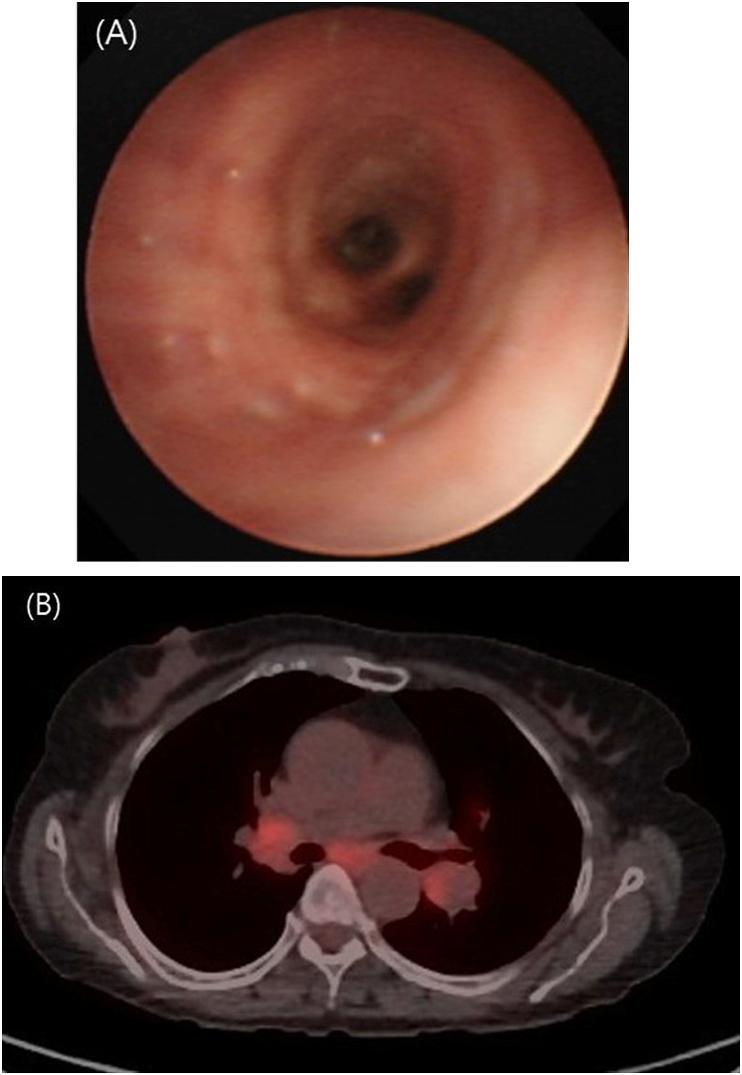

A 73-year-old female living in the rural area presented with chronic cough. She had multiple rounded nodules less than 1cm in size in both lungs, and bilateral mediastinal lymphadenopathy in chest images, which could be confused with metastatic cancer. Bronchoscopy did not show bronchial anthracofibrosis, and positron emission tomography (PET) scan showed F-18 fluorodeoxyglucose (F FDG) uptake. Surgical biopsy histology confirmed that the nodule was anthracofibrosis and the lymph node was reactive hyperplasia. Pulmonary function was accompanied by obstructive ventilatory defects, and clinical symptoms and lung function were improved after the use of inhaled corticosteroid and bronchodilator.

一名居住在农村地区的73岁女性因慢性咳嗽就诊。胸部影像显示双肺有多个直径小于1cm的圆形结节,双侧纵隔淋巴结肿大,可能会与转移性癌症混淆。支气管镜检查未显示支气管炭末纤维化,正电子发射断层扫描(PET)显示有F-18氟脱氧葡萄糖(FDG)摄取。手术活检组织学证实结节为炭末纤维化,淋巴结为反应性增生。肺功能伴有阻塞性通气功能障碍,使用吸入性糖皮质激素和支气管扩张剂后临床症状和肺功能得到改善。